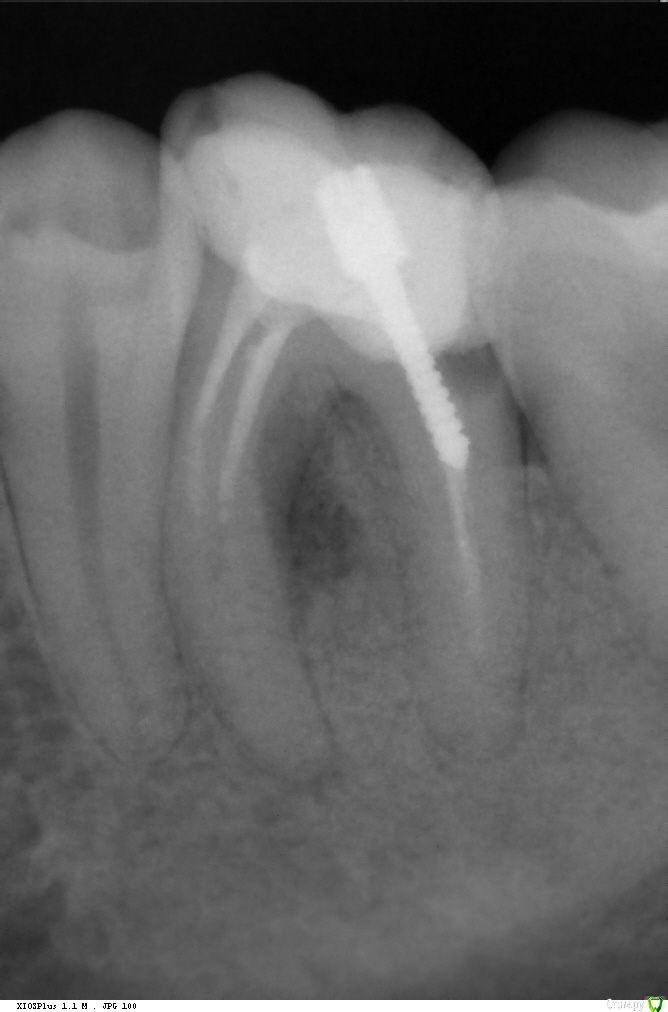

super Опубликовано 11 января, 2016 Поделиться Опубликовано 11 января, 2016 Доброго времени суток! Удаляю два зуба (снимки прилагаются). Будет ли возможность поставить импланты через несколько лет, если я откажусь от костного материала?В стоматологии расписали план, костный материал идёт опционально. Дескать, можно и без него, но лучше с ним, если планируете импланты (а я планирую через 2-3 года). Дополнительная информация:* Костный материал «БИ-ОСС» 0,5 гр.* 6-ка: пломба вылетела вместе со штифтом (снимок старый). Стоматолог сказал, что без шансов, надо удалять.* 7-ка: в 2-х стоматологиях сказали, что кариес корня и рекомендовали удалить. Спасибо :-) Ссылка на комментарий

red_butler Опубликовано 12 января, 2016 Поделиться Опубликовано 12 января, 2016 если судить только по снимку - за семерку бы поборолся 2 Ссылка на комментарий